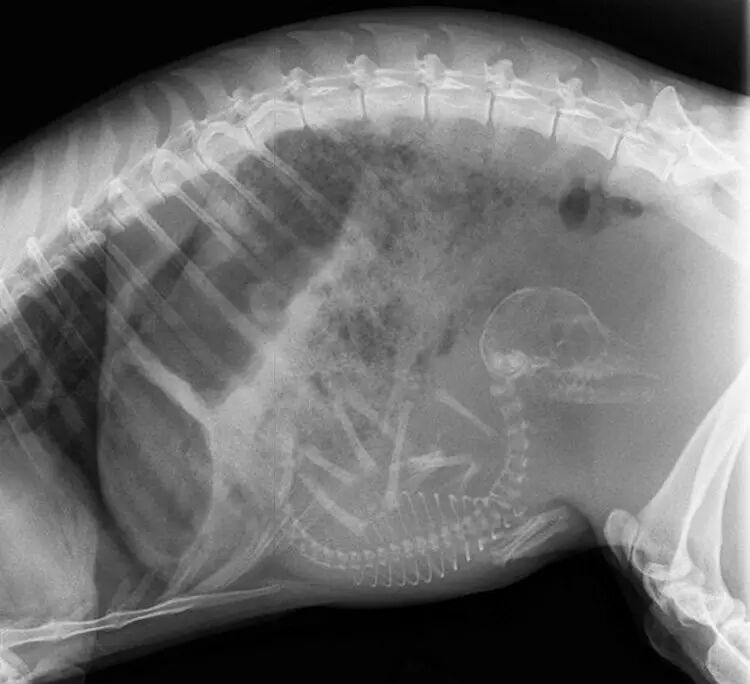

怀孕的猫,在怀孕后约45天,小猫的骨骼就会生长得能够用 X 光拍摄到。